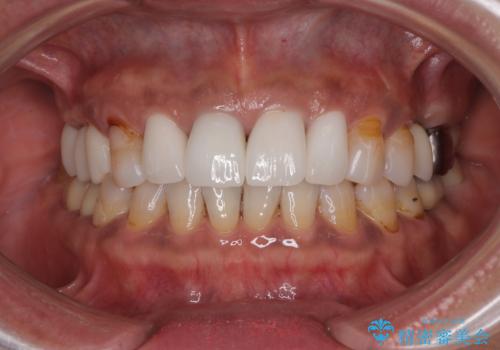

歯の大きさが小さいこと、隣の歯や反対側のセラミッククラウンの境目が見えていることなどから、前歯4本あるいは6本に対して、オールセラミッククラウンによる補綴治療をご提案しました。

見た目も大事だが、なるべく削りたくないとのことで、取り急ぎ4本を補綴治療し、今後犬歯の色などが気になることがあれば、追って対応することとしました。

6本同時に処置を行うと、矮小歯をより大きく見えるように工夫ができるというメリットがありましたが、4本のみの処置でも十分に満足をされていらっしゃいました。